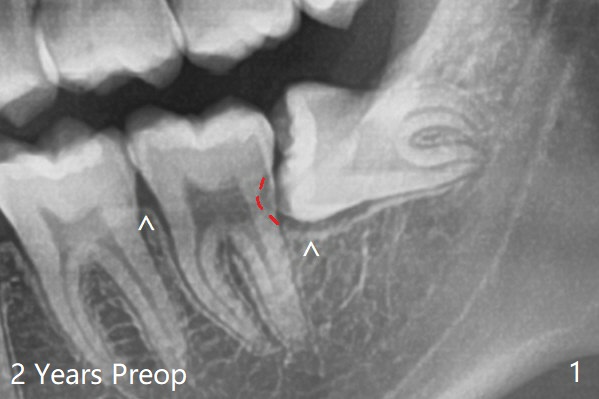

所以拔牙(多次切割)后,半块胶原塞放置于牙槽窝根尖(图二:C),而粘性骨粉牙槽窝牙冠,即第二磨牙远中(S),之上又放置半块胶原塞和两块PRF膜,促使伤口愈合,防止干槽症。